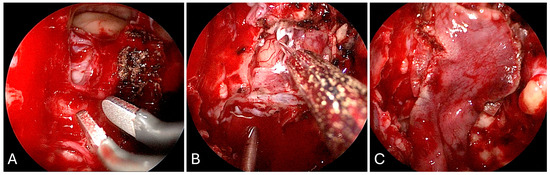

3.1.2. Illustrative Case

3.1.4. Illustrative Case